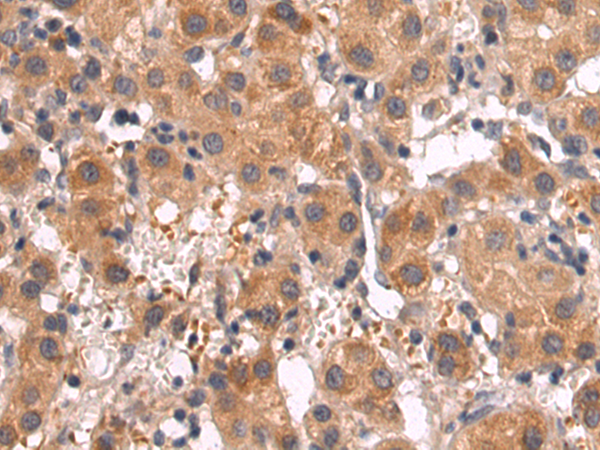

ELISA, IHC |

IHC positive control: |

Human tonsil |

IHC Recommend dilution: |

25-100 |